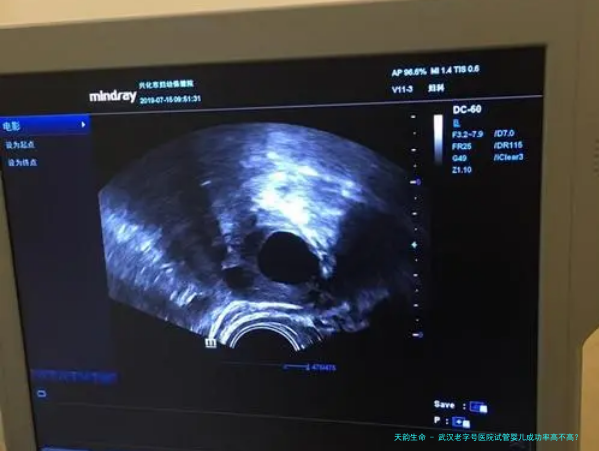

武汉老字号医院在试管婴儿领域拥有丰富的经验和尖端技术,因此其成功率相应较高。医院的医疗护理团队通过专业培训,能够为病人提供个性化的治疗方案,进而提高成功率。

武汉老字号医院拥有先进的设备和装置,能够为病人提供全局性的支持和服务。医院还注重病人的心理卫生,提供心理疏导和支持,帮助患者保持优秀的心态,增加成功的几率。